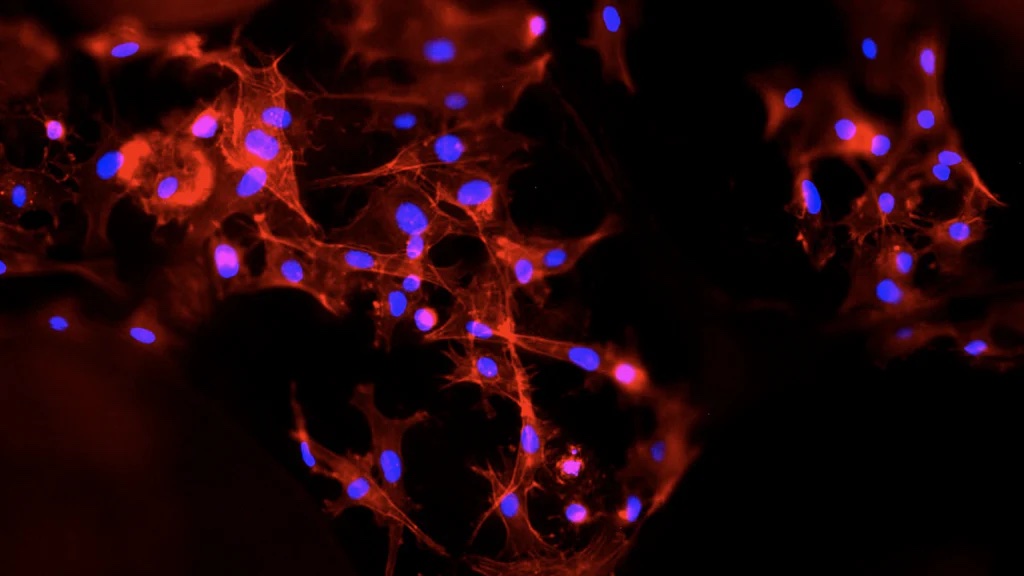

One of the more significant limitations of current synthetic bone grafts is insufficient cell migration into implanted bone grafts. In some cases, there is limited surface area for cell attachment, and in others, there is an insufficient supply of oxygen and nutrients for the frontage cell-line. Other products may be slow in increasing cell numbers inside the bone graft or may have a limited amount of blood vessel formation and blood circulation that assuages healthy cell growth. It is also not uncommon in cases of bone grafting for there to be slower or fewer cell differentiation. In all, these limitations correlate to the end result of poor bone regeneration and, in some cases, non-union between the new growth and the pre-existing bone.

In the same vein of thought of new bone growth, it is vital that implanted bone grafts are capable of providing mechanical integrity and nutrient support during the process of bone regeneration. A preemptive collapse of the graft could disrupt the healing process, and a lack of nutrients to migrating cells prevents healthy cell growth and the formation of capillaries and blood vessels. On a cellular level, the product should allow for ease of migration of cells, abundant surface for cell to anchor proper distribution, proliferation, and microenvironments for osteogenesis and angiogenesis. Additionally, bone grafts should be customizable to the specific needs of the patient undergoing a dental procedure or surgery and therefore more widely applicable to a variety of cases. OsteoGeneTM Tech strove to meet the criteria for an ideal synthetic bone graft with InRoad® spearheading the movement to more efficient alloplast products that overcome the limitations commonly seen for bone regeneration. InRoad®’s design meets all the qualifications to be considered an ideal bone graft and actually goes beyond simply meeting the minimum requirements. With its three-part structure, InRoad® has a superior sucking property compared to the top bone grafts available on the market today, which facilitates greater ease in cell migration and new bone growth at the site of application, and has no reported adverse effects during its testing period. At this current point in time, InRoad® is opening a new stage for bone grafts for both medical practitioners and patients alike.